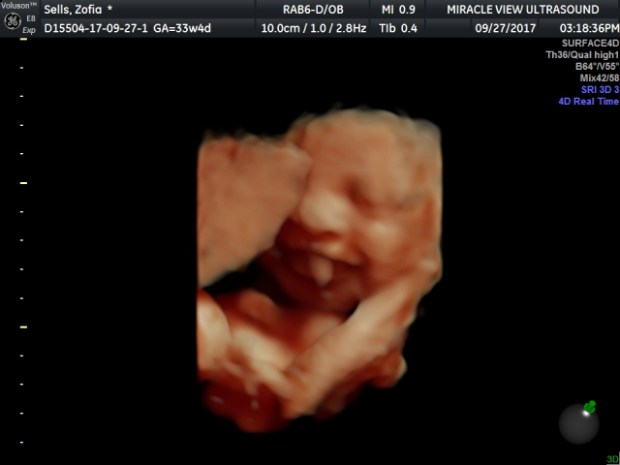

We also recently celebrated our three year anniversary and celebrated by having a 4D ultrasound done. By far, the best gift we could have ever given each other! Little mama smiled as soon as she heard daddy’s voice and it was all caught on video. She has a lot of hair like daddy did and from what we can tell, mommy’s cheeks and smile. 6 weeks to go!